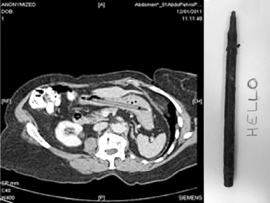

25 years ago a woman was standing on a set of stairs using a felt tipped pen to poke at something in her throat. Something else happened and she swallowed the pen. (She said she was standing on a set of stairs using a felt tip pen and a mirror to poke at a lump in her throat, I do not know. I suspect she does not know. In fact, I suspect if the pen hadn't caused her problems in the future it would have been an insignificant side note in the family history.) She told the doctor and her husband but they didn't believe her. (This story sounds taller and taller to me. I wouldn't have believed it. "Excuse me, Irene, you were doing what with what while on the what? Oh, please.") Fast forward to today when she had the pen removed and the pen was still capable of writing. (Note to manufacturer: Your pen obviously has staying power. You might want to buy it and put it in your museum of weirdness. Or maybe make a commercial with Charley Sheen. Either would work well.)

I see the pen. Also I see massive depression and two dogs playing ping pongwhile playing pinochle. (I was just playing with some Rorschachs's cards. If

you don't get this reference, it's because you didn't take Psych 101 in college

or you didn't watch One Flew Over the Cuckoo's Nest.)Oh, wait. I forgot this is a Christmas themed blog. I must go back and illustrate in my twisted manner.

Do you think the woman gave her permission for herx-rays to be posted ALL over the Internet? Because

if it was me who had a 25 year old pen lodged

inside me because I was obviously completely

effed up, standing on some stairs poking a pen

down my throat to see something about

my tonsils, I WOULD NOT give permission

to share with the entire freakin' world.What does this have to do with Christmas? Not a lot, but the story amused me and I did initially bring up the possibility of things shooting out of people's noses. (Wouldn't it have been funny if this woman had sneezed at the holiday dinner table and a 25 year old felt tip pen came shooting out of her nose? Well, probably not.)